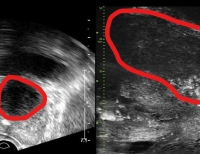

- 재발성 삼차신경통에 고해상도 MRI 기반 표적 설정 후 감마나이프 수술 정확도 향상

- 삼차신경통은 얼굴 감각을 담당하는 삼차신경이 주변 혈관에 눌리면서 극심한 통증이 반복되는 질환이다. 일반적으로 미세혈관감압술을 통해 혈관 압박을 제...